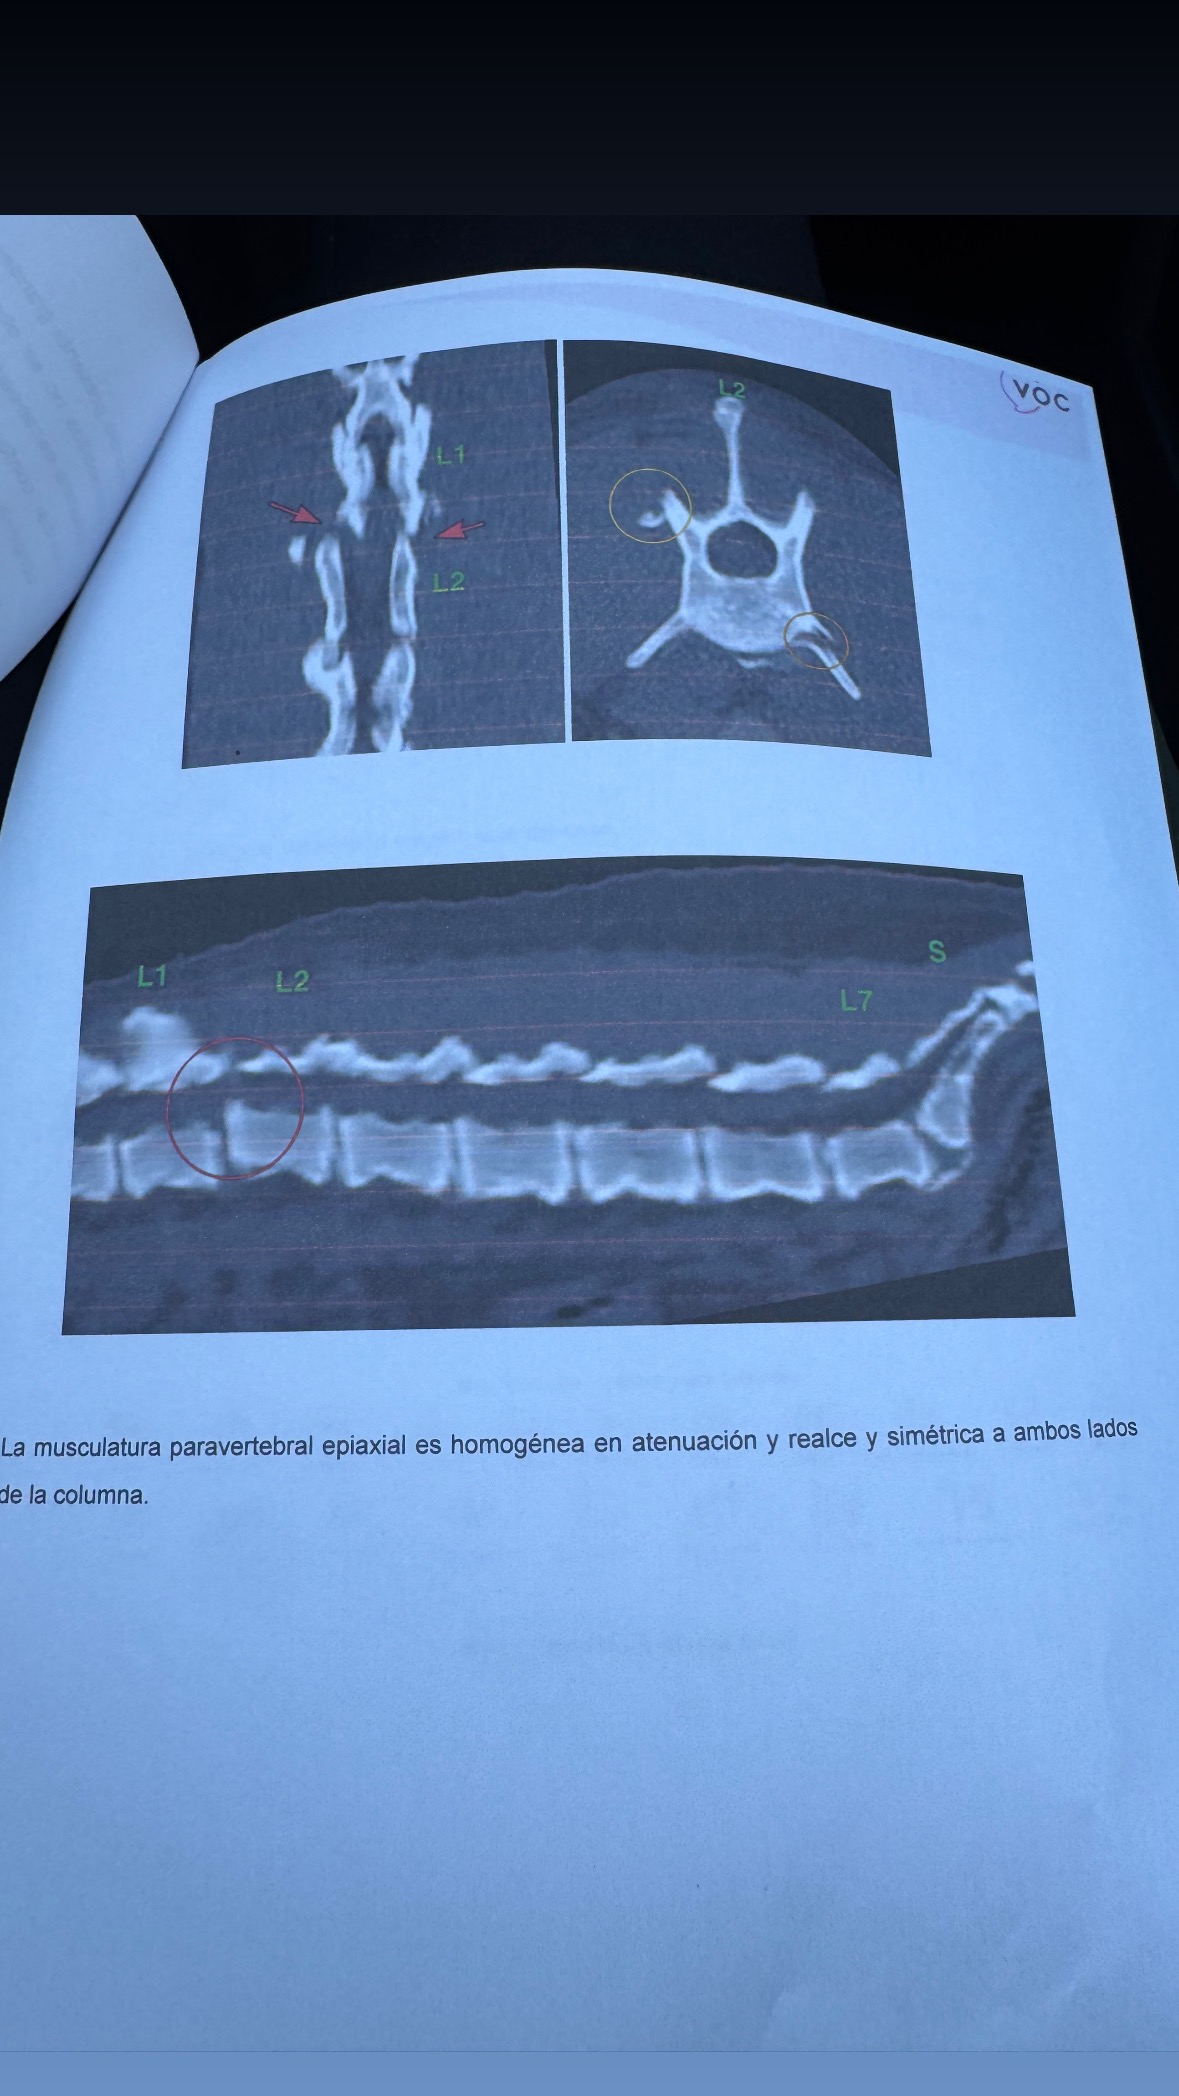

I had a car accident about 24 hours ago and I displaced a vertebrae and broke a femur. I’m in great hands right now and already had the spine surgery which went well. I need your help to cover the expenses and the rehabilitation.

I’ve already gotten through the spine surgery which was a success. I’m now waiting to operate on my femur at the beginning of the week.